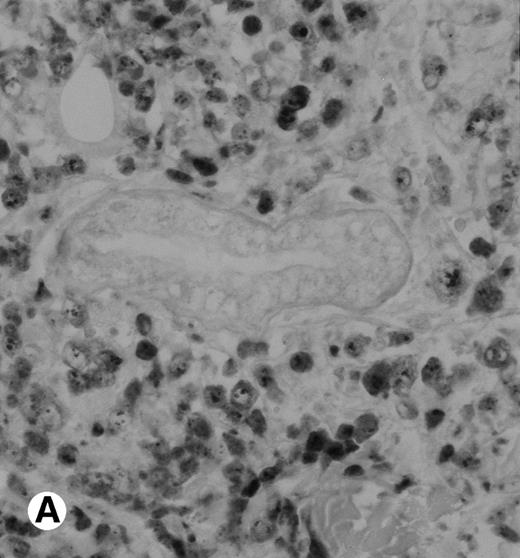

Immunohistochemical detection of chimeric NPM-ALK protein (×400). A case of CD30+ primary CLCL (case no. 8; A) and a case of CD30+ secondary CLCL (case no. 1; B) both with a positive NPM-ALK amplification by both RT-PCR and DNA-PCR were stained with the monoclonal ALK1 antibody. A granular cytoplasmic and strong nucleolar staining was observed on the large lymphomatous cells in these 2 cases.

The polyclonal anti-p80 provided a staining of some large cells of 1 of the 11 LyP (case no. 4). A cytoplasmic staining of lymphomatous cells was also seen in 4 of the 15 CD30+ primary CTCL (cases no. 5, 6, 8, and 9) and in 3 of the 11 CD30+ secondary cutaneous lymphomas (cases no. 1, 2, and 3). Keratinocytes or dendritic cells of the dermis were sometimes stained by anti-p80. All p80+ cases were previously shown to contain NPM-ALK transcripts by nested RT-PCR. However, not all cases with NPM-ALK chimeric transcripts were stained by p80+. No p80+ cells were detected in MF and BID sections. The staining with the monoclonal ALK1 antibody was cytoplasmic and nucleolar and restricted to tumoral cells of CD30+lymphomas. Only 1 case of CD30+ primary CTCL was ALK1+ (case no. 8; Fig 3). This case was 1 of the 2 cases with a positive standard RT-PCR amplification, whereas the other 1 was found to be negative for both p80 and ALK1 immunostaining (case no. 10). The 3 cases of CD30+ secondary CTCL with NPM-ALK transcripts were stained for ALK1 (cases no. 1, 2, and 3; Fig 3). No ALK1-immunoreactive cell was found in LyP sections and no labeling of the epidermis was observed. None of the cases with a negative NPM-ALK detection by RT-PCR and none of the MF and BID was found to be stained for ALK1.